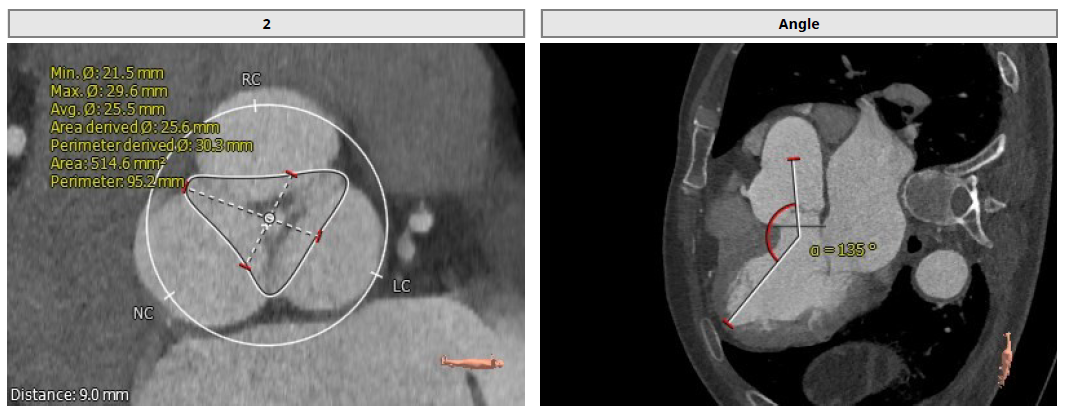

1.患者主动脉瓣三叶式,瓣叶基本等大,瓣叶增厚,瓣叶未见明显钙化;

2.患者主动脉瓣环周长折算直径约30.1mm;

3.患者双侧冠脉开口高度可LCA:16.2mm,RCA:21.8mm;

4.患者术中造影角度LAO:7°,CAU:1°。

Annulus: 30.1mm

环上结构折算直径:30.3mm ;主动脉瓣环夹角:135°

左冠高度:16.2mm;右冠高度:21.8mm

LVOT: 31.5mm;窦部直径:42.7/42.0/46.9mm

窦管交界:39.9mm;升主动脉:44mm

术中造影角度LAO: 7°,Caudal: 1°